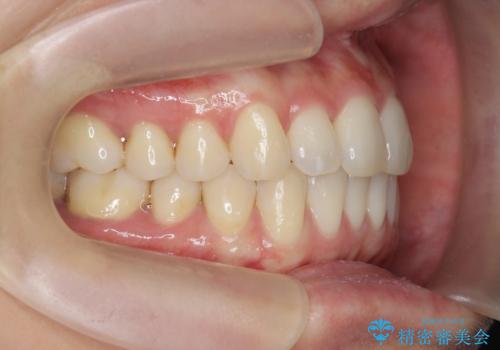

前歯のねじれを改善 マウスピース矯正インビザライン

左側の奥歯は後方移動を行うことで、理想的な噛み合わせに整えるとともに、前歯の突出感も同時に改善することができました。